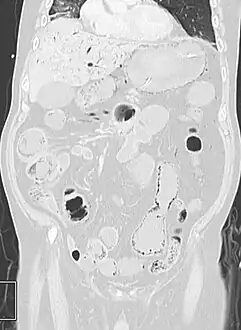

Pneumatosis intestinalis at computed tomography in intestinal ischemia. Lung window for better representation of the gas deposits in the intestinal walls. Coronal reconstruction.

Pneumatosis intestinalis in the coronal computed tomography in lung window. It can be seen next to gas entrapment in the bowel wall and gas in the stomach wall and in numerous vessels, including the portal vein into the liver.